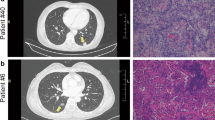

In this study, LUAD, LUSC and LUBN were diagnosed by both CT and immunohistochemical staining. Representative CT and pathological images of patients with LUAD, LUSC, or LUBN and healthy controls are shown in Fig. 2a and b. Exosomes isolated from the plasma of all enrolled individuals were characterized by transmission electron microscopy (TEM), nanoparticle tracking analysis (NTA), protein profiling and Western blotting [19, 20]. Among these approaches, TEM is the gold standard for determining the presence of exosomes. Our results indicated that exosomes in all groups were dish- or cup-like vesicles with a diameter of 50–100 nm and a lipid bilayer. During the freezing and rewarming process of plasma at – 80 ℃, large extracellular vesicles will rupture, forming small cell membrane fragment structures, leading to background differences (Fig. 2c). NTA also indicated that the average diameter of the exosomes in all groups was 100 nm (Fig. 2d), consistent with a previous study on exosome analysis (119–21). CD81, PDCD6IP, CD9 and CD36 were present in exosomes, as determined by MS [21,22,23] (Fig. 2e). Finally, Western blotting was performed to detect exosomal biomarkers (CD9, HSP70, CD63 and GM130) in 4 randomly selected patients. CD9 was highly expressed in 3 patients, and CD63 and HSP70 were highly expressed in all 4 patients. Exosome negative protein was not expressed (Fig. 2f). These results confirmed the specific characteristics of exosomes from all enrolled individuals.

Identification and characterization of extracted exosomes. Pathological (a) and CT (b) images from randomly selected patients with LUAD, LUSC, or LUBN and NLs. TEM images of (c) and NTA (d) results for plasma exosomes. e Typical exosomal proteins CD81, PDCD6IP, CD9 and CD36 were validated by MS. f Detection of exosomal positive protein markers CD9, CD63, HSP70, and exosomal negative protein marker GM130 by Western blotting.(The blotting membrane is customized based on the specific molecular weight)